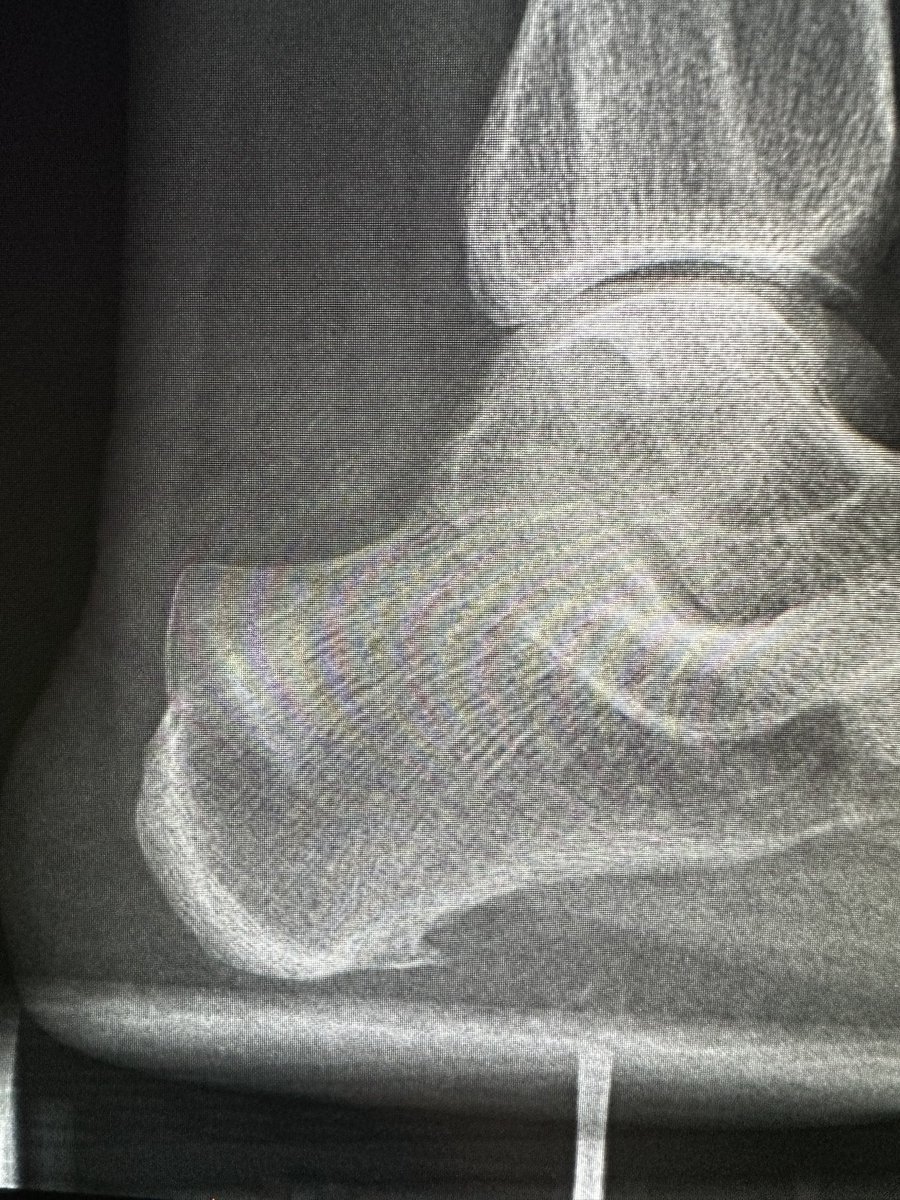

Nice example of a haglund deformity, insertional tendinopathy and partial tear with reactive bursitis

RJ tweet mediaRJ tweet media